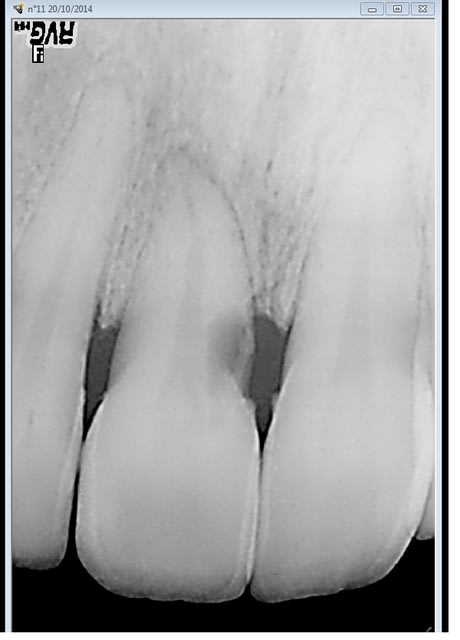

La patiente a la trentaine,

cette 11 est nécrosée et en plus présente une carie/résorption externe très fortement sous-gingivale.

Ca se sauve comment, ou implant ?

dans ton cas, l'apex est aussi salement raccourci (trauma ? )